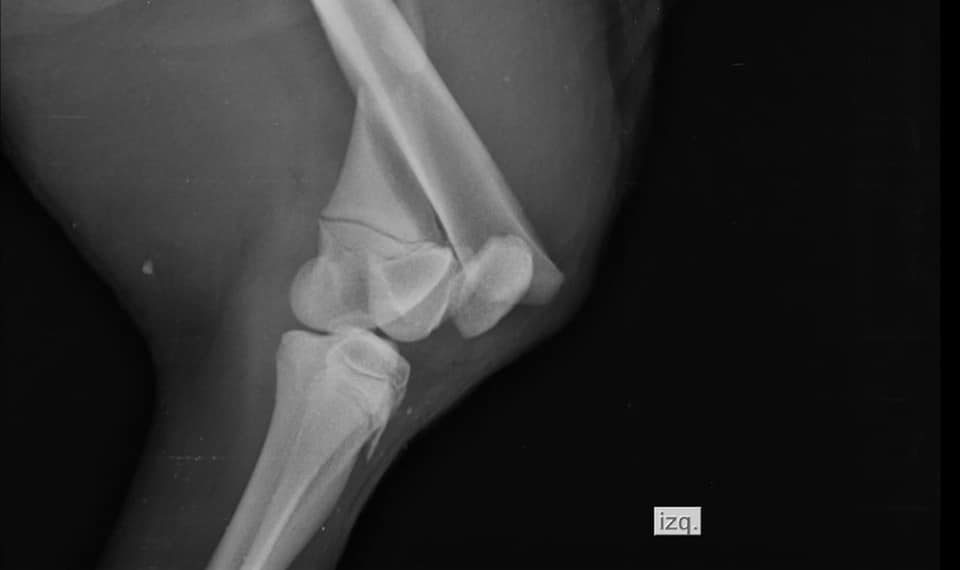

«Lo trajeron al refugio, donde procedimos a limpiarlo y revisarlo, constatando golpes varios y una posible fractura. Se procedió a una intubación con sonda para la primera alimentación a fin de estabilizarlo, y luego rayos X, donde se constato la fractura del fémur, que estaba inflamado también. Luego de una completa estabilización mediante alimentación con sonda, a los 8 días de haberlo recibido, la inflamación había bajado, y se le pudo hacer la cirugía correspondiente. Que yo sepa, nunca se hizo nada similar en Paraguay», explicó.

Finalmente tras varios días de tratamiento y en una situación más estable, ayer pudieron realizar la cirugía que necesitaba para la fractura sufrida y fue todo un éxito, luego de despertar de la anestesia el hormiguero pudo tomar agua por si solo. Ahora queda un tiempo largo de recuperación.